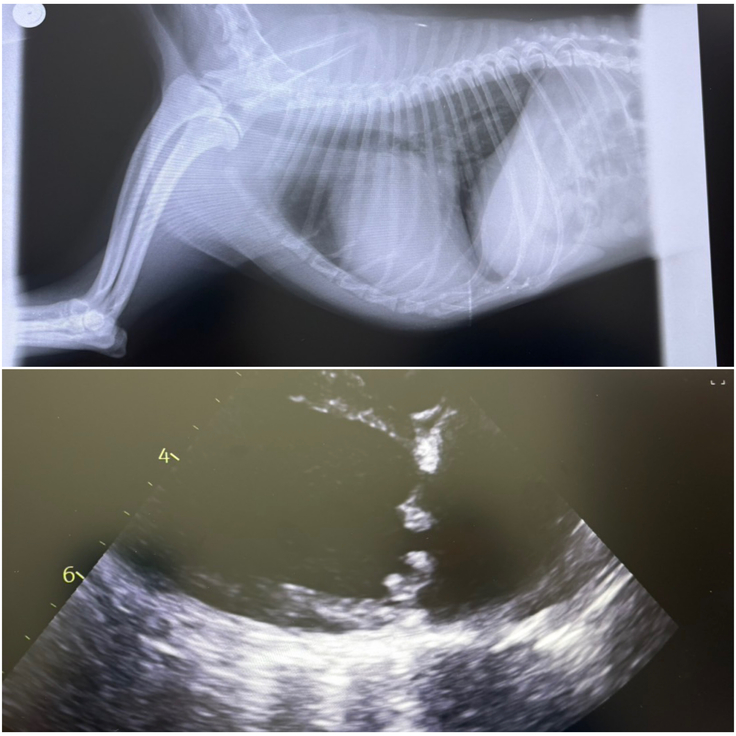

現在、心臓病(僧帽弁閉鎖不全症)の投薬治療をしています。

2022年10月、アポの心臓に雑音が見つかり、「僧帽弁閉鎖不全症」と診断されました。

【僧帽弁閉鎖不全症とは】

獣医師の説明では、心臓の僧帽弁が正常に閉鎖できなくなり、血液が逆流してしまう病気で、進行すると肺水腫などの心不全を引き起こすことがあるということでした。

診断結果は左心房破裂。

僧帽弁閉鎖不全症(ステージC)の治療のため手術を受けます。

さらに、三尖弁閉鎖不全症(右心房の血液の逆流)、気管虚脱(気管が潰れて呼吸困難になる病気)、腎臓に腫瘍もあり、今後の不安もあります。